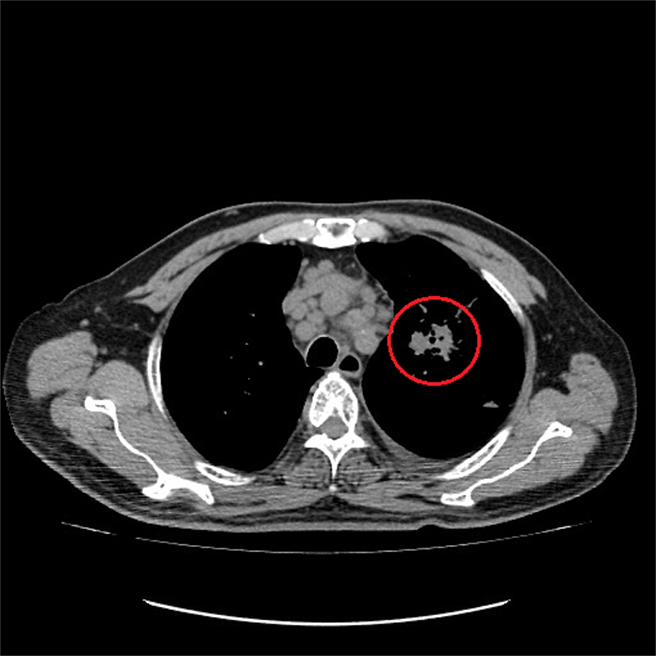

治疗六个月肺腺癌已明显缩小到3公分。(台中澄清医院提供/冯惠宜台中传真)

这位患者以右胸疼痛难忍求诊,一度怀疑是心肌梗塞的前兆,经心电图检查并无异状,却在X光检查发现左上肺好大一片阴影,再以肺部电脑断层扫瞄,确定他的肺部肿瘤已达7.2公分,经病理切片检验证实是罹患凶恶的肺腺癌。

江雅惠指出,患者服用标靶药物一个月后,肺腺癌已明显缩小了一半,再经跨科精准治疗六个月后的回诊电脑断层影像追踪,显示他的癌细胞移转部位控制的不错,没有再恶化的现象,过去的胸痛情况已消失,而肺腺癌已缩小至3公分左右,证实这样的疗程是有很好的治疗结果。